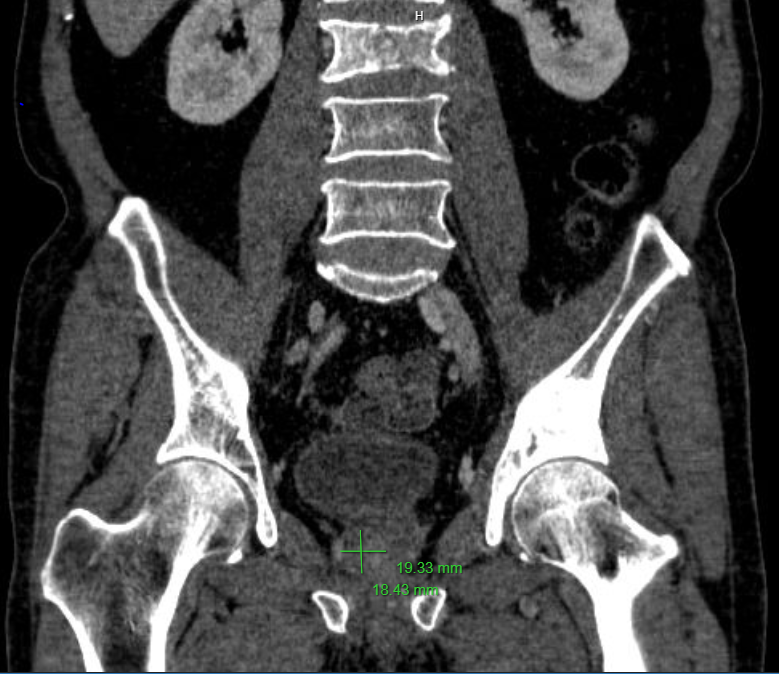

- Chụp CT ổ bụng từ vòm hoành đến tiểu khung, trước và sau tiêm thuốc cản quang:

+ Tiền liệt tuyến vùng chuyển tiếp có nốt ngấm thuốc mạnh sau tiêm, kích thước 18x19mm. Cạnh tĩnh mạch chậu trong trái có hạch kích thước 9x12mm.

+ Các tổn thương dạng tiêu xương, đặc xương thân, cuống L3, xương mu, ngành ngồi mu hai bên, ổ cối bên trái.

Hình ảnh CT trước và sau tiêm thuốc cản quang: Các tổn thương dạng tiêu xương, đặc xương thân đốt L3 và ổ cối trái